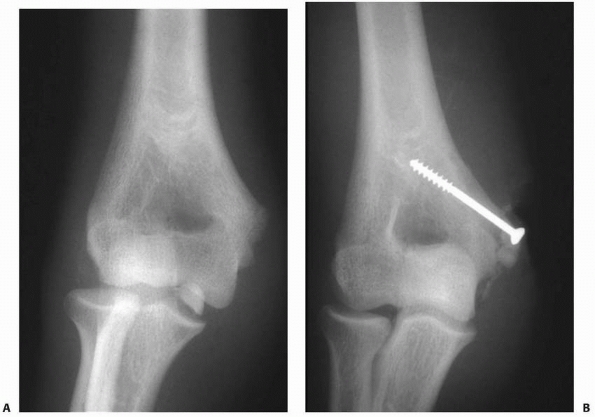

![]() |

FIGURE 15-1 A. Injury film of a 7-year-old with an undisplaced fracture of the lateral condyle (small arrows). Attention was drawn to the location of the fracture because of extensive soft tissue swelling on the lateral aspect (white arrows). B.

Because of the extensive soft tissue injury, there was little intrinsic stability, allowing the fracture to become displaced at 7 days (arrow). |